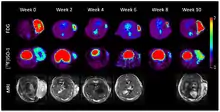

Exogenous sigma-2 receptor ligands have been altered to be neuronal-tracers, used to map cells and their connections. These tracers have high selectivity and affinity for sigma-2 receptors, and high lipophilicity, making them ideal for usage in the brain.[5] Because sigma-2 receptors are highly expressed in tumor cells and are part of the cell proliferation mechanism, PET scans using sigma-2 targeted tracers can reveal if a tumor is proliferating and what its growth rate is.[5]